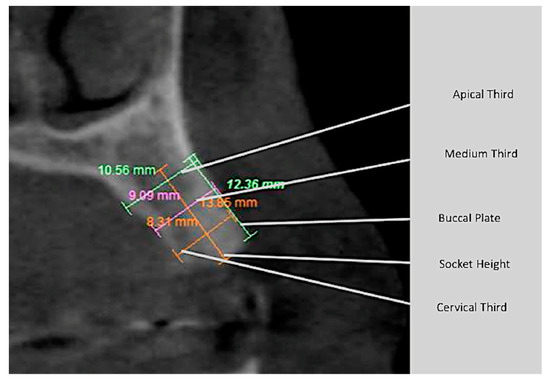

2.6. Tomographic Analysis

| Parameter | Before | After | ||

|---|---|---|---|---|

| Mean | Standard Deviation | Mean | Standard Deviation | |

| Buccal plate | 5.55 | 1.73 | 6.01 | 2.33 |

| Socket height | 9.10 | 1.50 | 8.69 | 1.48 |

| Cervical third | 7.46 | 0.73 | 6.57 | 1.12 |

| Medium third | 7.80 | 1.00 | 7.15 | 1.10 |

| Apical third | 8.10 | 1.17 | 8.18 | 1.32 |

| Buccal plate | 7.37 | 2.32 | 8.49 | 1.95 |

| Socket height | 9.96 | 1.36 | 10.32 | 2.07 |

| Cervical third | 7.68 | 0.94 | 7.57 | 0.92 |

| Medium third | 8.10 | 1.29 | 8.02 | 1.31 |

| Apical third | 8.78 | 1.26 | 8.64 | 1.46 |

| Parameter | Control | Test | P Value | ||

|---|---|---|---|---|---|

| Mean | Standard Deviation | Mean | Standard Deviation | ||

| Buccal plate | 0.46 | 3.04 | 1.11 | 0.91 | 0.417 |

| Socket height | −0.41 | 0.76 | 0.35 | 1.16 | 0.049 |

| Cervical third | −0.89 | 0.71 | −0.11 | 0.73 | 0.008 |

| Medium third | −0.64 | 0.57 | −0.50 | 0.32 | 0.002 |

| Apical third | 0.09 | 0.60 | −0.14 | 0.69 | 0.348 |